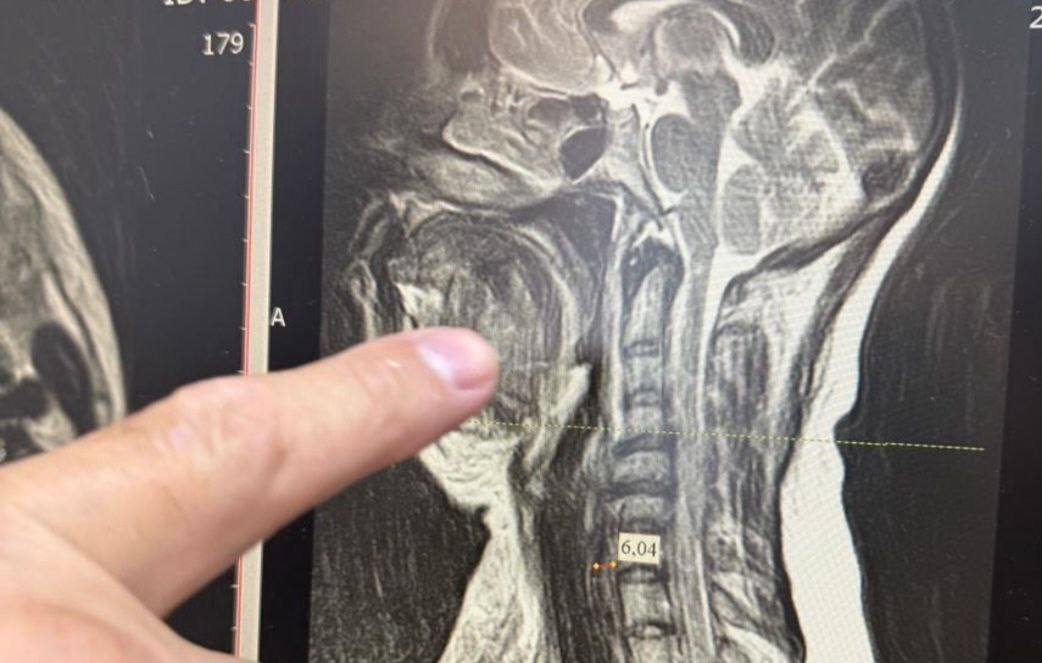

В Ессентуках врачи спасли женщину поступившую к ним в критическом состоянии из за разрушенного зуба 35 летняя женщина поступила в больницу с высокой температурой и обширным отёком шеи который затруднял дыхание Причиной всему стал разрушенный зуб Как оказалось врачи столкнулись с одной из самых сложных форм осложнения двусторонней флегмоной окологлоточного пространства которая при отсутствии своевременного лечения в большинстве случаев заканчивается летальным исходом Пациентке провели экстренную операцию Затем три дня она провела в реанимационном отделении подключённой к аппарату ИВЛ Пятнадцать дней понадобилось медикам для того чтобы вернуть женщину к полноценной жизни ее уже выписали из стационара